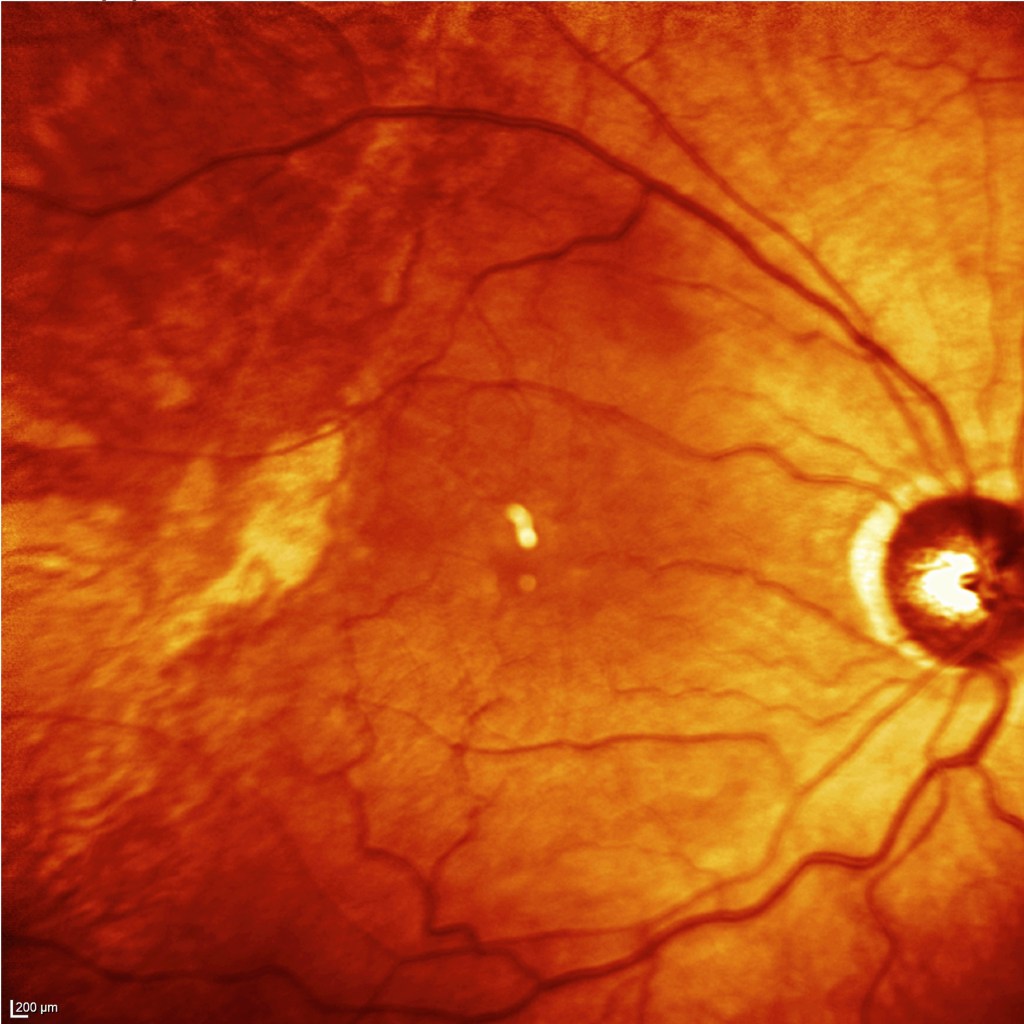

Podemos ver las retinografías previas a la cirugía y en estado de hipotonía. En hipotonía se experimentó una dificultad para enfocar las imágenes. Se aprecian también cambios en área del nervio óptico..

La OCT de la zona valvulada y las OCTs retinianas previas y en hipotonía: